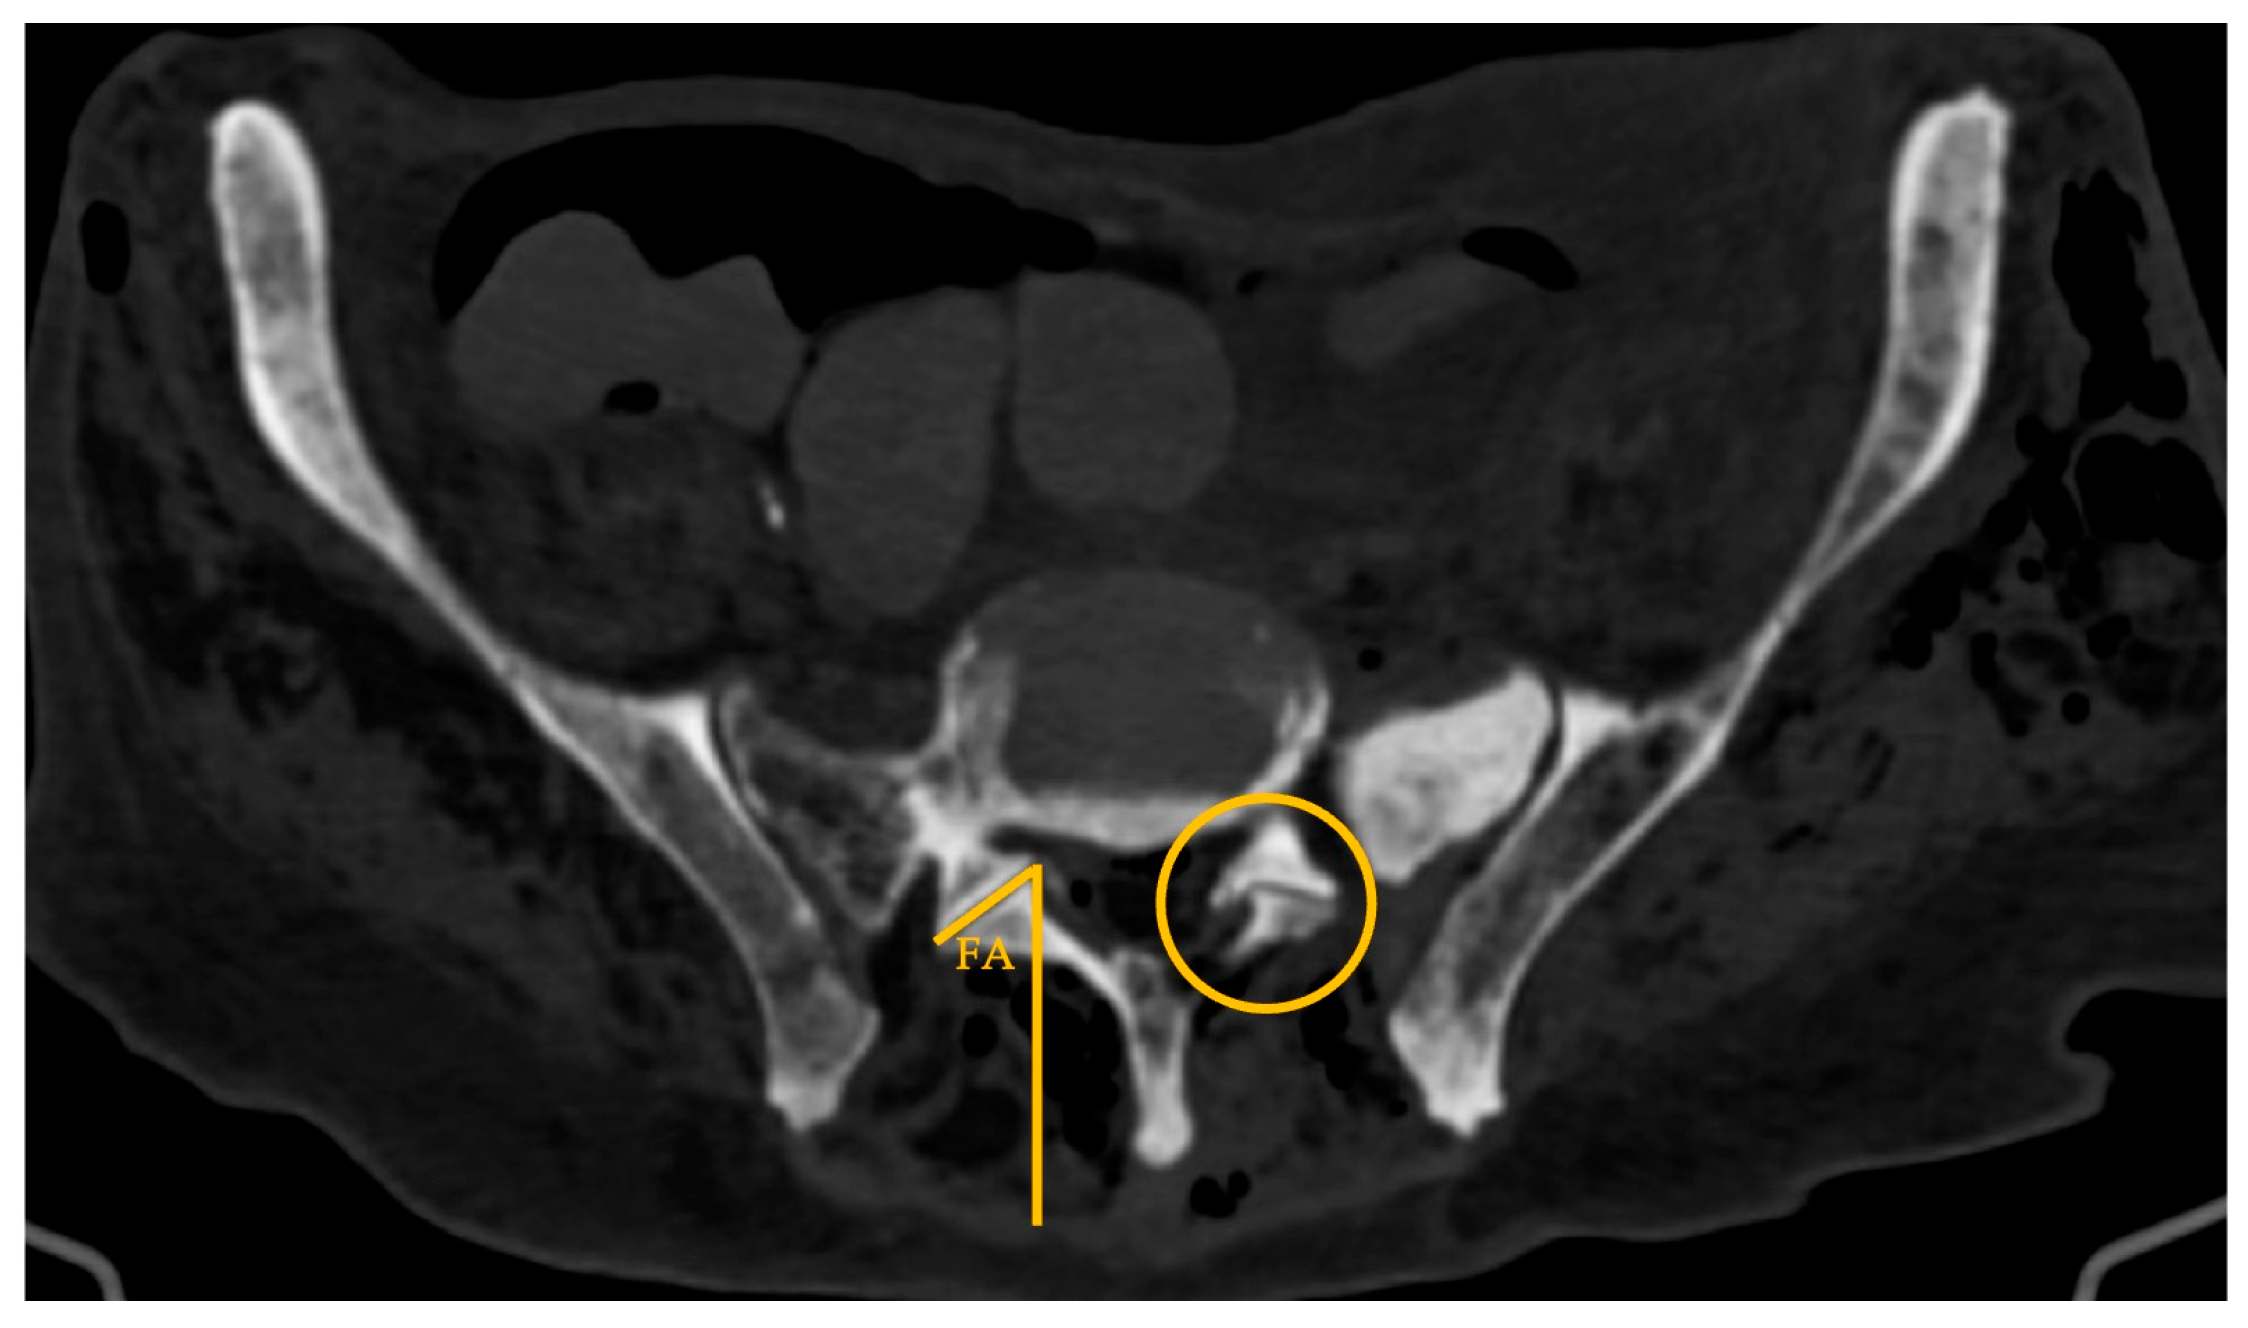

• Approach angle (AA): angle between the midline and the vector (V) tangential to the iliac crest that crosses the most anterior point of the L5-S1 disc space (axial plane at IVD space; Figure 5)

• MinL5-V: minimum distance from the ventral ramus of the L5 spinal nerve to V (axial plane; Figure 5)

The mean AA (Figure 5) was 35.2±5.0°. An EF vector (V) tangential to the iliac crest that crosses the most anterior point of the L5-S1 disc space defined a workable corridor to the L5-S1 disc in 75% of the cases (18/24 sides). These cases had significantly greater AA (29.9±3° vs 37.2±4°; p=0.02) and despite not statistically significant, larger TP to sacrum distances, greater EF-areas, and increased minL5-V values were found. However, in 44% (8/18) of cases with a workable corridor on CT based on AA the distance to the ventral ramus of the L5 spinal nerve was inferior to 5mm.

The median minL5-V distance was 5.0(7.1) mm, with no statistically significant gender (p=0.788) or sacral morphology (p=0.429) variation. This parameter was zero in 8 out of 24 cases (33%), meaning direct overlap between the vector V and the ventral ramus of the L5 spinal nerve.

Figure 5. Lumbar spine CT – axial plane; *: ventral ramus of the L5 spinal nerve; dotted yellow lines: marking of the approach angle (AA; angle between the midline and the vector (V) tangential to the iliac crest that crosses the most anterior point of the L5-S1 disc space; solid orange line: minL5-V (minimum distance from the ventral ramus of the L5 spinal nerve to vector line).